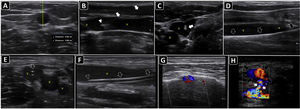

The maximal site of fluid accumulation is often eyeballed by ultrasonography (although the smallest fluid depth can be used to quantify the effusion), and the distance from the skin to the parietal peritoneum and visceral peritoneum is measured to aid in the selection of the needle length and estimate the depth of insertion (Fig. 4A).63

Ultrasound-guided paracentesis. A) Ascites is observed (asterisk), and the distance from the skin to the effusion and to a bowel loop (b) is obtained. B) The inferior epigastric vessels (boxes) are delineated into the abdominis rectus sheath using a linear probe on two-dimensional and color Doppler imaging; s, skin; sct, subcutaneous tissue; m, rectus abdominis muscle; asterisk, ascites. C) The insertion site is marked on the skin, and puncture is performed under static guidance. D) Real-time ultrasound-guided paracentesis; arrows, needle shaft; arrowhead, needle tip; asterisk, ascites. E) A locking pigtail catheter is observed within the ascites (asterisks). The arrow indicates the body, whereas the arrowhead indicates the tip of the pigtail.

Using a linear probe, the abdominal wall vessels should also be identified and excluded from the needle trajectory (Fig. 4B).

ProcedureEither static or real-time technique can be used. Similar to ultrasonound-guided thoracentesis, the static technique is preferred. The insertion site should be marked immediately before performing the procedure (Fig. 4C), and the patient should remain in the same position between marking the site and performing the procedure, given that free-flowing peritoneal fluid and abdominal organs, especially loops of the small bowel, can easily shift when a patient changes position or takes a deep breath.62

Real-time ultrasound-guided paracentesis (in-plane or out-of-plane) (Fig. 4D) is best suited for obese patients, for patients with small fluid collections, or when performing the procedure near critical structures, such as loops of the small bowel, liver, or spleen.62

When there is a need to evacuate fluid, a pigtail catheter is preferred, although a central catheter can be used in selected cases.64 The catheter position could also be confirmed using ultrasound (Fig. 4E).

In transverse and longitudinal views, soft-tissue fluid collections are measured, as well as the distance to the skin, to estimate the needle depth of insertion and to choose an adequate needle length (Fig. 5A,B). Color Doppler aids in defining the presence of vascular structures near the lesion, to avoid puncturing when inserting the needle.

Ultrasound-guided aspiration of soft tissue collections and arthrocentesis. A) Soft tissue fluid collection is identified and measured. B) Distances are measured to estimate the needle depth of insertion and length to be used. C) Technique for finding the suprapatellar articular recess of the knee and its corresponding ultrasound images; p, patella; t, cuadriceps tendon; f, femur; asterisk, fat pad (articular recess). D) Knee effusion is indicated by the symbol #. E) Real-time ultrasound-guided arthrocentesis of the knee, obtaining a purulent fluid. The arrowhead indicates the bevel of the needle that reached the articular effusion. F) Real-time ultrasound-guided aspiration of soft tissue collection. The needle is indicated by arrows.

Ultrasound anatomy of each joint should be well known for assessing effusion. Given its frequency and ease of access, knee ultrasound is reviewed herein. With the linear probe placed longitudinally above the patella and the probe marker pointing cephalad, the superior portion of the patella, quadriceps femoris tendon (long axis), fat pad, and femur should be observed (Fig. 5C). The effusion will be located below the quadriceps tendon and above the femur (Fig. 5D). Once fluid effusion is recognized, the probe is rotated 90 degrees into a transverse view so that the probe marker faces to the patient's right side. The distance from the skin to the effusion is then measured to estimate the needle depth of insertion and length to be used.

ProcedureReal-time technique is used to aspirate soft-tissue collections and perform arthrocentesis. The out-of-plane and in-plane approaches are selected on a case-by-case basis. For example, aspiration of abscess and knee arthrocentesis are best performed using the in-plane approach (Fig. 5E and 5F), whereas the out-of-plane approach is preferred for aspiration of effusion from the wrist joint. A fully sterile barrier technique is required to do so.